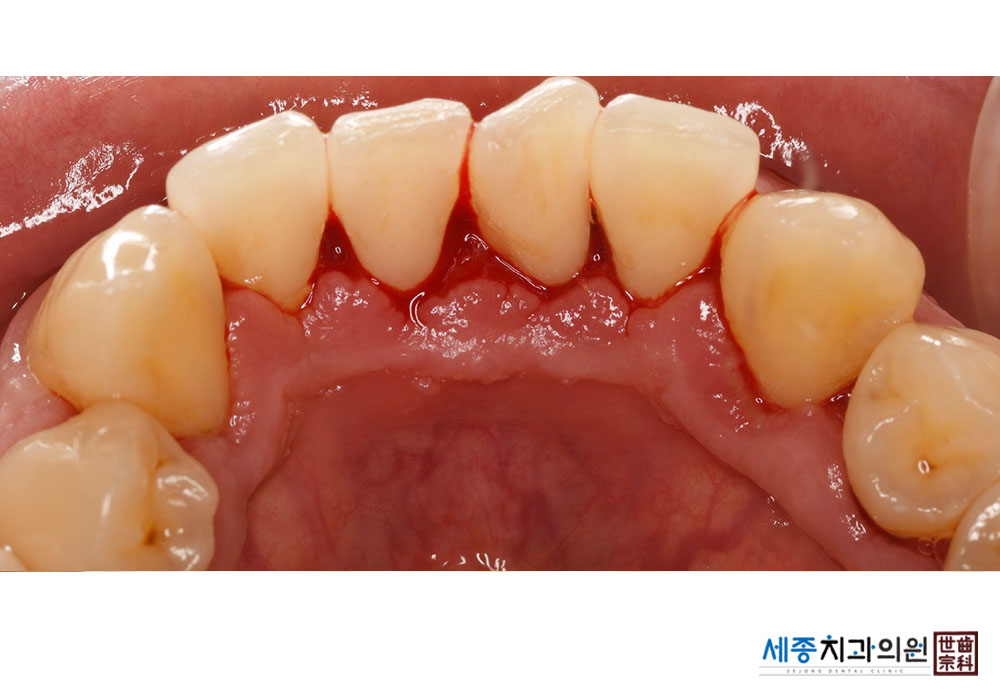

[스케일링] 치주질환 예방 스케일링

치료전 : 2023-07-25

치료후 : 2023-07-25

가글마취&저주파 스켈러를 사용한 스케일링